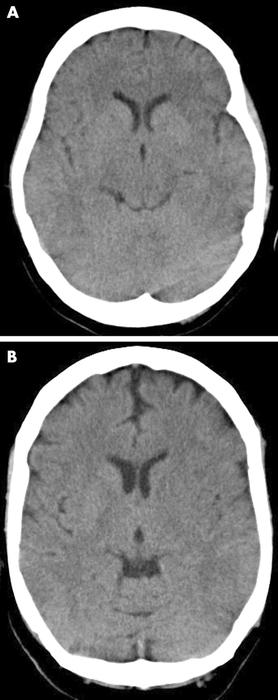

[Figure caption and citation for the preceding image starts]: Non-contrast CT scan of brain showing sub-acute isolated left basal ganglion infarction with left frontal horn mass effectCourtesy of BMJ Case Reports 2009; doi:10.1136/bcr.10.2008.1139 [Citation ends].

[Figure caption and citation for the preceding image starts]: Two examples of early ischaemic changes on CT in sub-three hour ischaemic stroke. (A) Acute left middle cerebral artery (MCA) ischaemia with loss of insular ribbon, and hypodensity of tail of lentiform nucleus. (B) Similar changes in a different patient, with hypodensity of entire lentiform nucleus, some hemispheric sulcal effacement, and compression of lateral ventricle caused by hypodensity of caudate headMuir KW et al. Neurology, Neurosurgery & Psychiatry 2005; 76: iii19-iii28; used with permission [Citation ends].